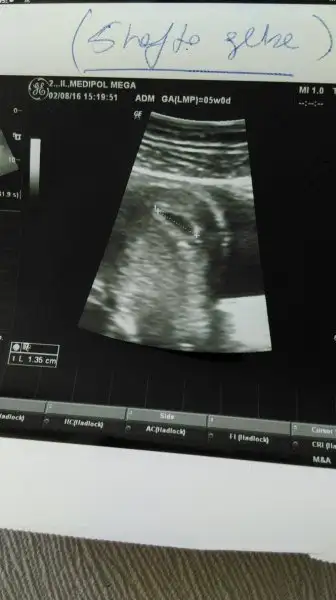

ultrasondan gördük canım. tam 5 haftayı doldurup gittim ben

Eklentiler

• 13682387_10153961325189209_1421089393_o.webp

13682387_10153961325189209_1421089393_o.webp

12,1 KB · Görüntüleme: 70